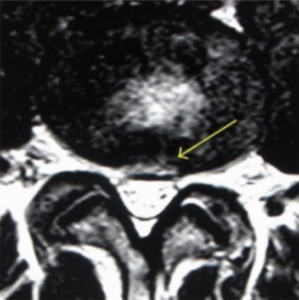

Since not all disc degeneration leads to DBP, efforts have been made to identify radiographic findings that predict progression to discogenic pain and aid in diagnosis.19,25–27 One such finding is the presence of Modic changes on MRI, which represent vertebral bone marrow lesions. Modic changes have been demonstrated to have a high specificity for DBP.25 High-intensity zones (HIZ) on MRI have also been identified as a risk factor for DBP, although with less sensitive and specific (Figure 1).26 Additionally, CT with provocative contrast discography has demonstrated a relationship between discogenic pain and annular tears.19

MRI is useful for diagnosing DBP with particular attention to HIZ, nuclear signal, disc height, disc contour, and bone marrow intensity change.33,34 Disc degeneration on T2 weighted MRI appears as hypointense discs due to decreased signal intensity.28 HIZ on MRI are areas of hypodensity located on posterior annulus fibrosus in lumbar scans. It is theorized that inflammation of the annular fibrosus fissure causes the HIZ to appear and is the source of pain in DBP (Figure 1). One study found that TNF-alpha and CD-68 positive cells were higher in number in HIZ than in controls.35 However, HIZ, has good sensitivity but low specificity for DBP.36 Modic changes on MRI aid in the diagnosis of DBP as intensity changes on T2 and T1 weighted sequences are used to classify scans of vertebral endplates and subchondral bone into categories describing inflammatory changes, fatty degeneration of bone marrow, and sclerosis of subchondral bone (Figure 2).36 The combination of different MRI parameters increases its utility as a diagnostic tool.37